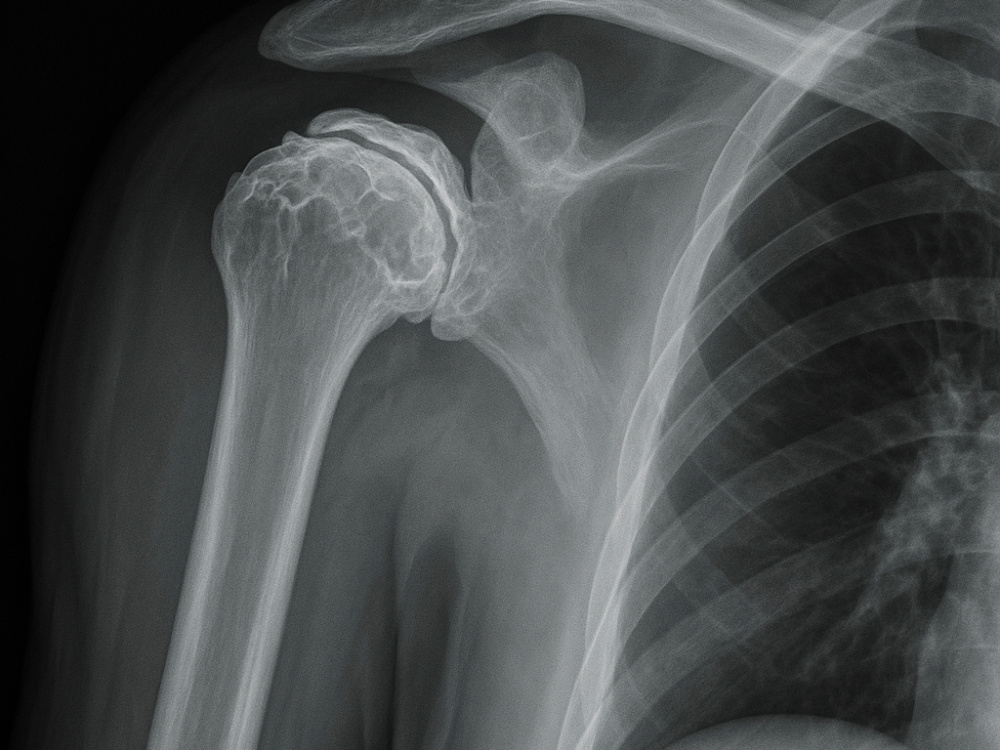

Si les traitements conservateurs n'ont pas donné les résultats escomptés, une prothèse d'épaule (arthroplastie) peut être la solution. Cet acte chirurgical est de plus en plus revendiqué par les patients souffrant de douleurs chroniques et de mobilité limitée.

La Turquie se propose aujourd'hui comme une destination de premier plan pour cette procédure, alliant expertise médicale, technologies de pointe et coûts abordables.